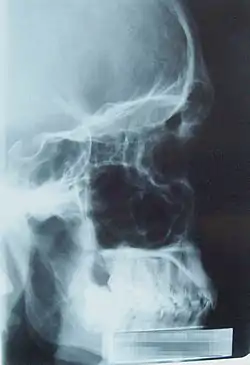

![]() Lateral projection of the paranasal sinuses | |